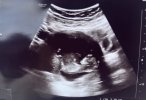

O superU nas po wizycie już,dzidziuś ma się dobrze,już były podejrzenia ws plci (podobno chłopiec), choć to dopiero 11 tydzień.uspokoilam się,że serduszko bije![]()

A wiadomo jakie tętno było ? Mniej jak 140 czy więcej?U nas po wizycie już,dzidziuś ma się dobrze,już były podejrzenia ws plci (podobno chłopiec), choć to dopiero 11 tydzień.uspokoilam się,że serduszko bije![]()

Cudowne wieści, gratulacje @SzklanaKulka i @anusia87, piękne dzidziusieTo i ja swojego bejbuna pokaże! A co![]()